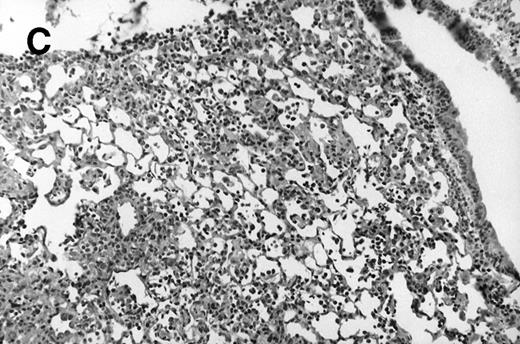

Allogeneic transplanted mice (B10.BR → CBA) with GVHD and, as controls, allogeneic transplanted mice without GVHD and syngeneic transplanted mice (B10.BR → B10.BR) were infected intranasally with HSV-1 at 12 weeks after transplantation. As an additional control, age-matched normal CBA mice were infected as well. Histological examination of lungs was performed in mock-infected mice and in mice at day 7 after infection. Allogeneic transplant recipients with GVHD showed increased pathology (Fig 1). Scores reflecting the periluminal histopathologic changes were significantly higher (P = .05; Student's t-test) in allogeneic transplant recipients with GVHD, when compared with control mice (Fig 2). The periluminal histopathologic scores were also higher in allogeneic transplant recipients with GVHD, when compared with normal CBA mice, at days 4, 10, and 14 after infection (data not shown). No significant differences were observed in the scores reflecting the parenchymal histopathologic changes (data not shown). Because the results in syngeneic transplanted mice were very similar to those in allogeneic transplanted mice without GVHD, the latter, which are the most appropriate control for procedural effects and for the effect of GVHD, and normal CBA mice, were used as controls in further experiments.

Allogeneic transplant recipients with GVHD showed increased pathology. Photomicrographs of lung sections stained with hematoxylin and eosin show evidence of increased pathology in infected allogeneic GVHD mice. (A) Normal CBA, mock-infected, original magnification × 25; (B) normal CBA, mock-infected, original magnification × 100; (C) normal CBA, infected, original magnification × 40; (D) normal CBA, infected, original magnification × 100; (E) allogeneic GVHD, mock-infected, original magnification × 10; (F) allogeneic GVHD, mock-infected, original magnification × 75; (G) allogeneic GVHD, infected, original magnification × 10; (H) allogeneic GVHD, infected, original magnification × 100.